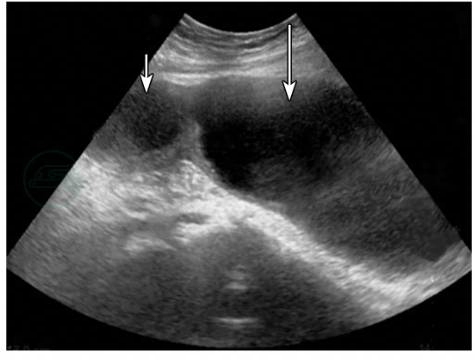

1.子宫积血(常见为处女膜闭锁所致)

①阴道积血:阴道呈囊状膨隆,内见较多积液伴密集细小点状回声(为黏稠血液);②阴道、子宫积血:下段膨大部分为阴道积血,上段为增大的子宫伴宫腔积血,二者之间以较窄腔隙相连通(为宫颈管)(图16-22)。

图16-22阴道、子宫积血

子宫稍大,宫腔内见液性区(短箭头所示);阴道呈囊状膨隆,内见较多积液伴细小点状回声(长箭头所示)。